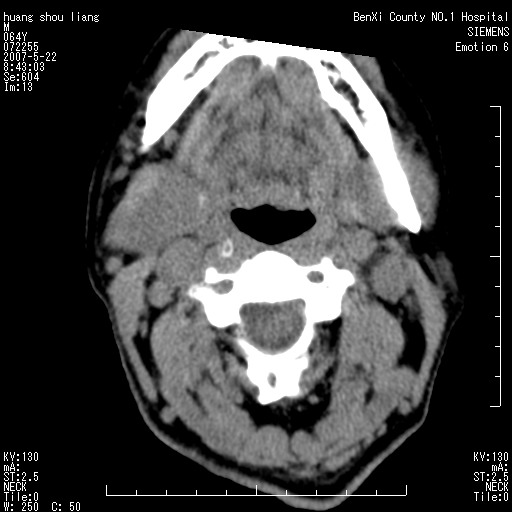

男性,64岁。颈部包块8年。最近增大。

对不起大家,可能是片子发太多有点乱,正常腮腺在下颌角的外侧,颌下腺在下颌体的中部内侧,本例在下颌角内侧偏下,和腺体一点关系都没有,从vrt和mpr上可以很明显看出来,再者肿块是好多粘连在一块的,大家在仔细看看,左侧可能也是吧,我还是考虑为肿大的淋巴结融合在一块,但性质??????

右侧腮腺下部均匀软组织密度肿块,外形不规则,与周围组织分界清晰,考虑右侧腮腺混合瘤或多形性腺瘤。

大家好,病理结果出来了,如大家所说,颌下腺混合瘤。

唉,解剖没学好吧,我诊断错了,不过还是有些不理解回去我在多看看书,谢谢大家的参与,以后我还会奉献好的病例。